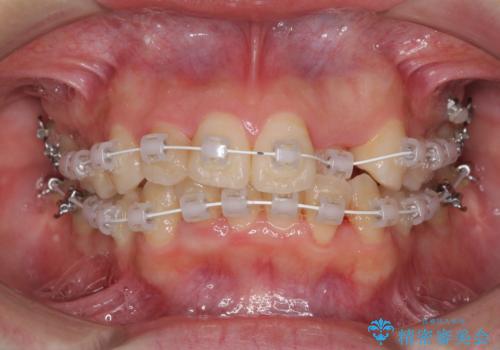

短期間で終了 デコボコをワイヤー矯正で解消

- 審美装置

- 1年3ヶ月